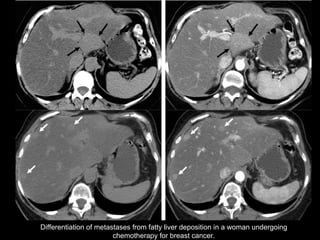

Differentiation of metastases from fatty liver deposition in a woman undergoing chemotherapy for breast cancer.

Hypovascular Metastases  and Lymphoma The differentiation of focal or multifocal fat deposition from hypovascular metastases and lymphoma in the liver  may be difficult .  The clinical manifestations and imaging features such as  lesion morphology ,  location , and  microscopic fat content  usually permit a correct diagnosis. Chemical shift GRE imaging  may be necessary to assess the amount of intralesional fat.

Differentiation of metastasesfrom fatty liver deposition in a woman undergoing chemotherapy for breast cancer.